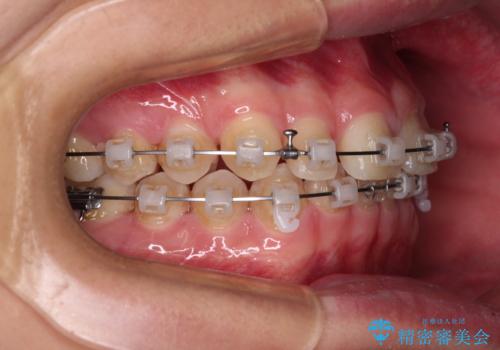

隙間とデコボコを治したい ワイヤー装置による矯正治療

- 矯正装置

- クリアブラケット

- 前歯のデコボコと隙間を気にして来院された患者様です。

治療手段としてはワイヤー装置でもインビザラインでも可能でしたが、インビザラインの自己管理は自信がないとのことで、ワイヤー矯正により隙間を閉じていくこととしました。

隙間の原因は舌の突出癖であったので、舌癖改善のためのトレーニングを指導しながら治療を進めて行くこととしました。

舌の突出癖がなかなか改善されず、治療開始時よりも隙間が大きく開いてしまう時期がありましたが、最終的にしっかりと閉じて終了することができました。